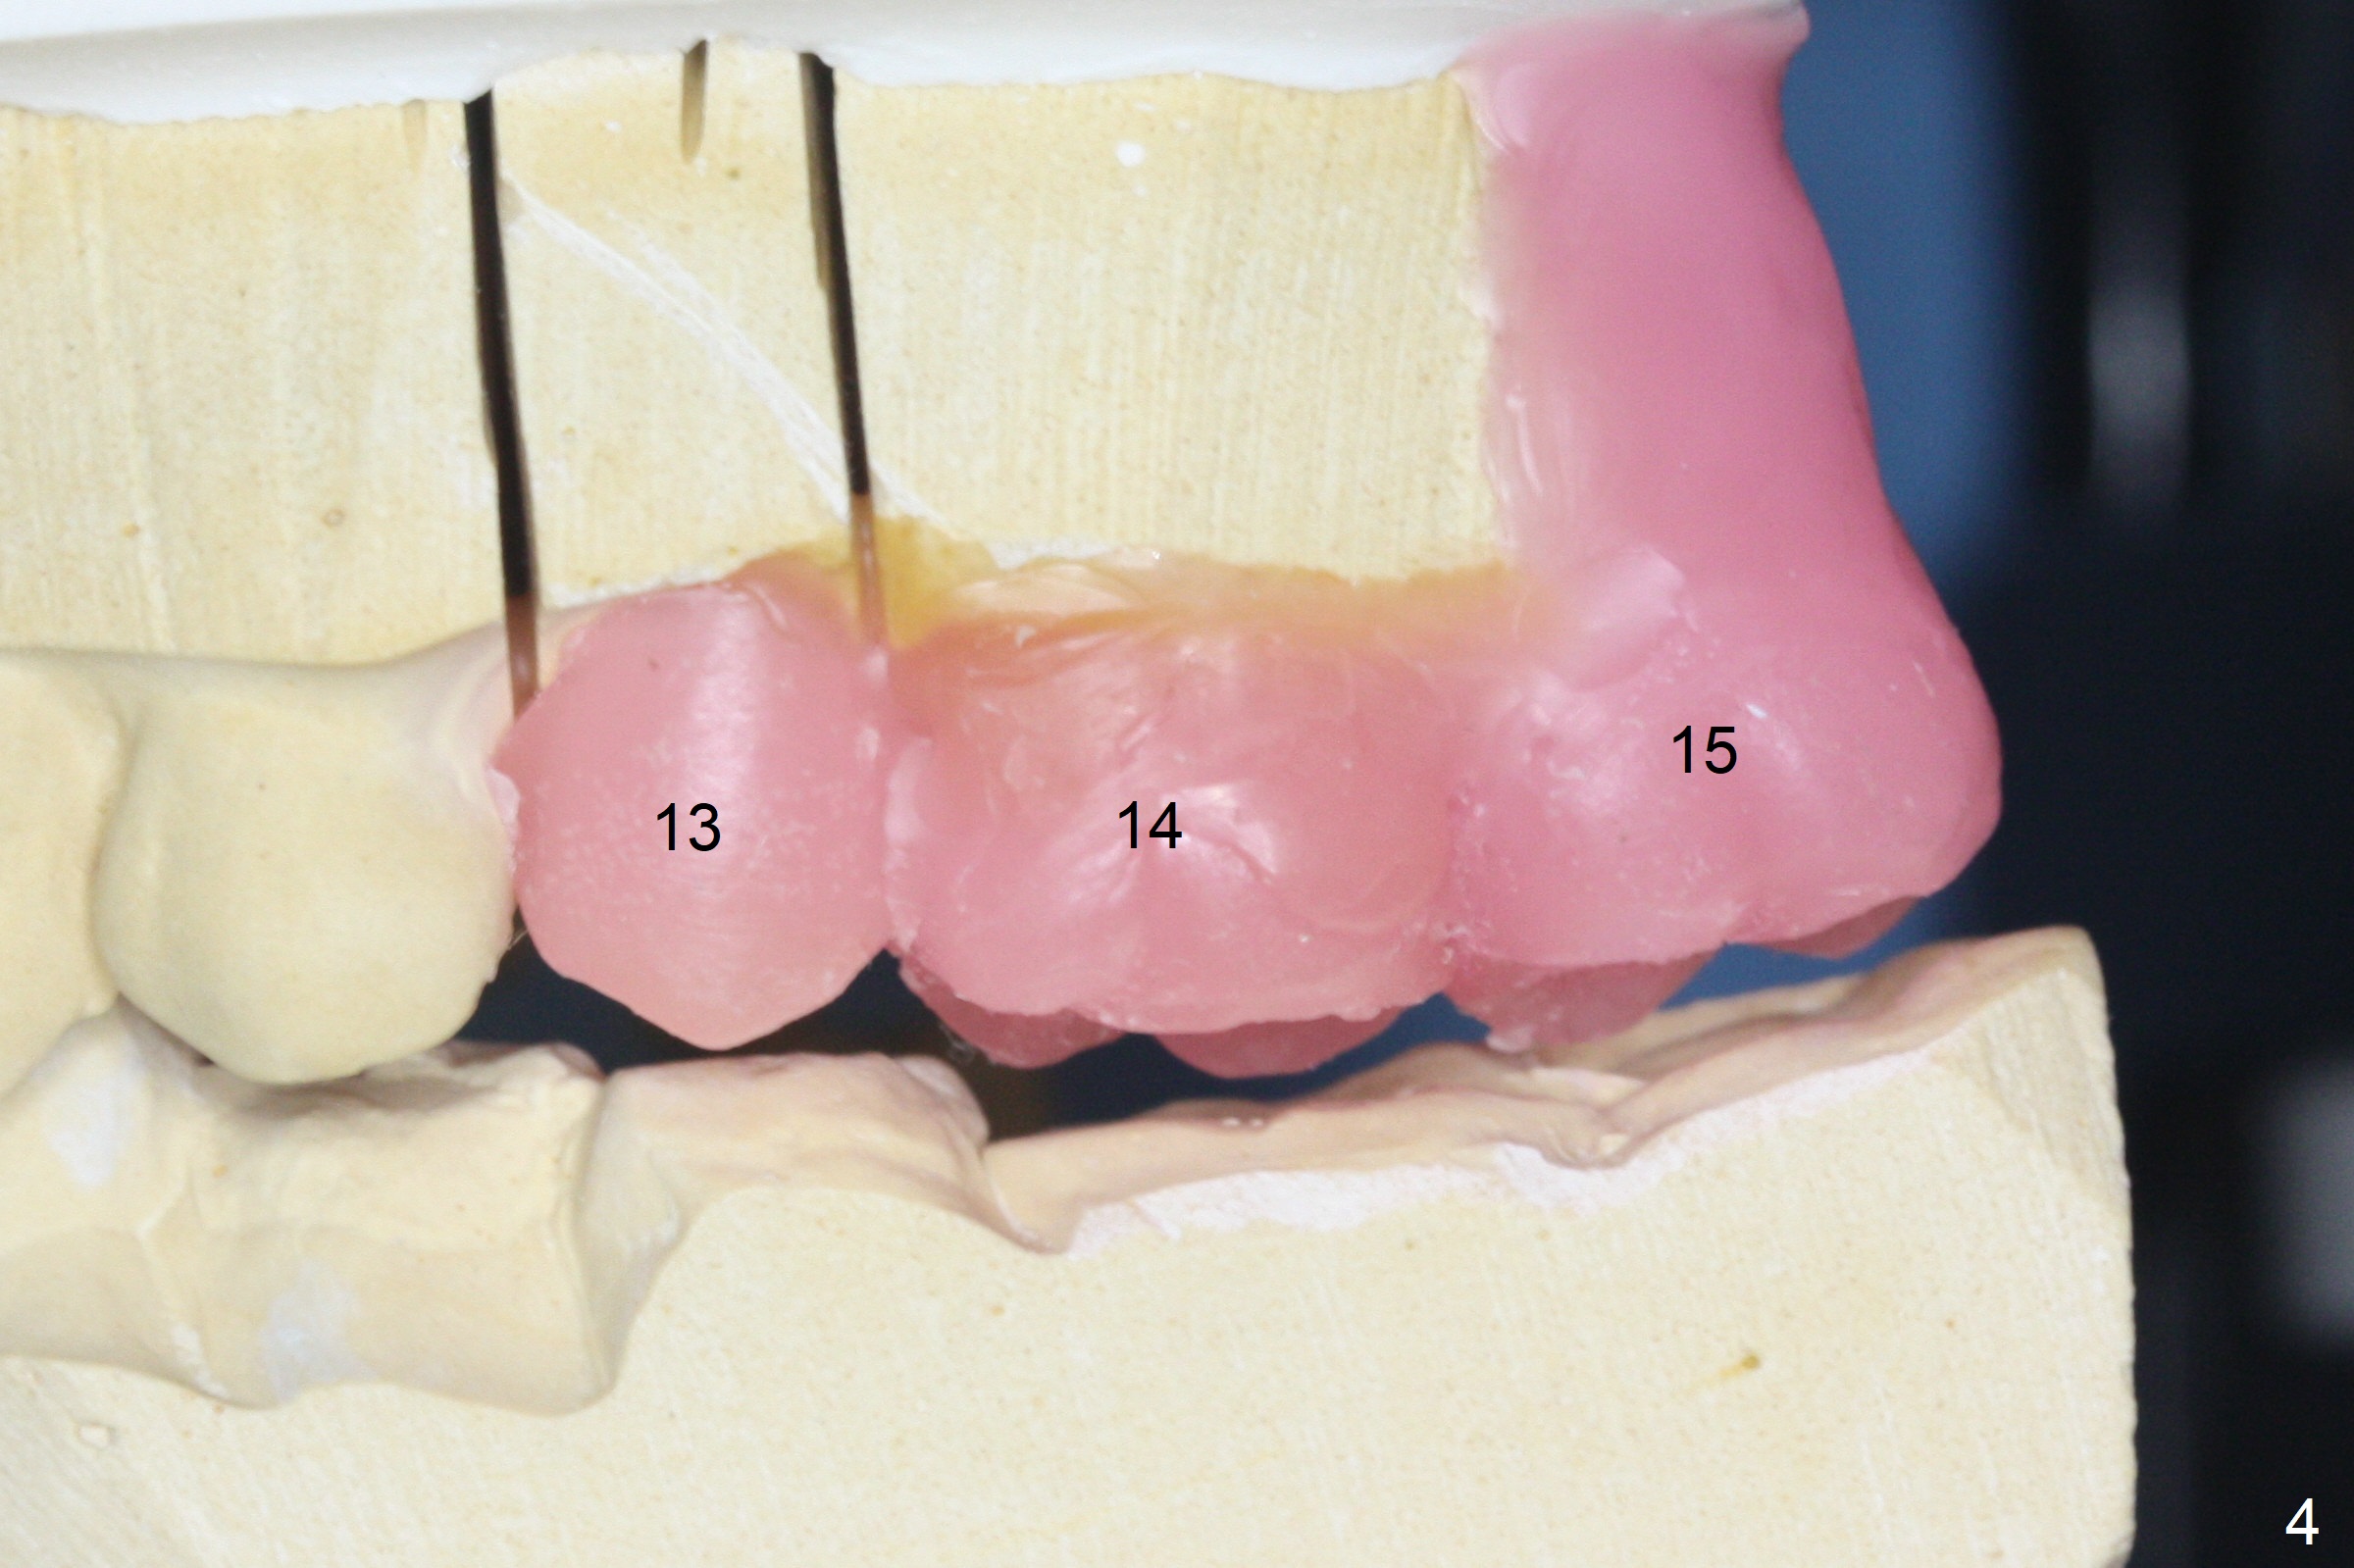

A 73-year-old man lost #15 implant 4 months ago with socket preservation (Fig.1 (taken 1 month post bone graft (^)). The tooth #14 was extracted with socket preservation ~ 9 months ago. The sites should be not so dense that Magic Split will be used to start osteotomy for 7 mm (Fig.2). Prior to this step, use 1.5 mm or starter drill and surgical stent to mark the initial osteotomy. BEB is followed by Magic Expanders (1 mm longer each). Implants are expected to be 9 or 11 mm long (Fig.3,4).